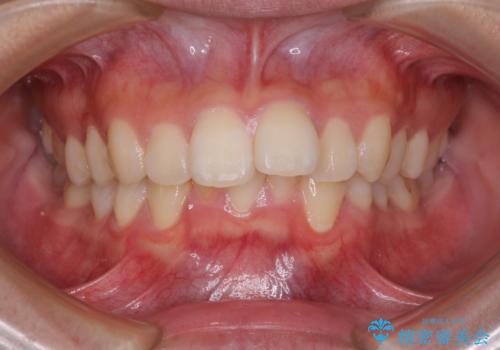

【審美装置】前歯のがたがたを治したい

担当医 河口智英

【審美装置】前歯をきれいにしたい